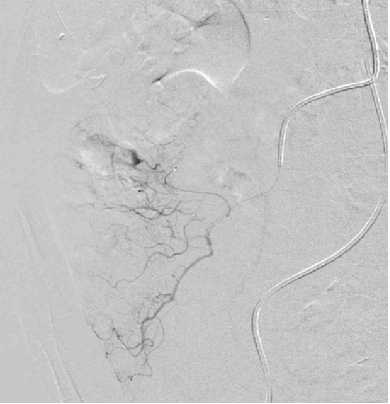

Position of the microcatheter in the vasa recta

2. 在肠壁(vasa recta),弹簧栓子最好的位置

下消化道出血,微弹簧栓子直小动脉栓塞